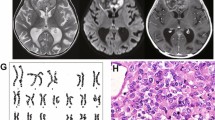

A 3-year-old boy was seen in Genetics clinic due to pervasive developmental delay, submucous cleft palate, and sensorineural hearing loss. Clinical findings are summarized in Table 1. He was noted to have gastroesophageal reflux in the newborn period. His gross motor milestones were normal although his fine motor skills were delayed. He had significant language difficulties. His growth parameters were normal. He had upslanting palpebral fissures, small epicanthal folds bilaterally, and simple ears. There was mild facial asymmetry, with the right ear approximately one-half centimeter smaller than the left ear (Fig. 1a). He had small joint hyper-extensibility and mild tapering to his fingers. Genetic analysis performed at that time did not reveal an underlying diagnosis, as his chromosome analysis and FISH for a probe (TUPLE1) in the DGS/VCFS region were normal.

a Patient 1 at 4 years of age. Note the upslanting palpebral fissures, mild facial asymmetry, and simple ears. Hearing aids are present due to his sensorineural hearing loss. b Patient 2 at 1 year of age. Note the upslanting palpebral fissures similar to patient 1. She also has a down-turned mouth and flat midface, but normal ears

At 5 years of age he presented with weight loss and hematuria. He was diagnosed with a left renal rhabdoid tumor, which was considered metastatic to the right ventricle of the heart and lungs. During these investigations a small muscular ventricular septal defect was found. The child was treated with a left nephrectomy, excision of the cardiac lesion and radiation to the left renal area and lungs. He was treated with a number of courses of chemotherapy, but died of complications due to the lung lesions 15 months following diagnosis.

Patient 2

A female infant was born prematurely at 34 weeks with a V-shaped cleft palate and atrial and ventricular septal defects that subsequently closed. She remained hospitalized for 2 weeks after birth. Her first year of life was complicated by gastroesophageal reflux and difficulty feeding, secondary to her cleft palate. At 12 months, she was hospitalized for a history of weight loss and fussiness. At that time she was noted to have multiple dysmorphic features including short upslanting palpebral fissures, Brushfield spots, malar flatness, mild fifth finger clinodactyly, as well as the V-shaped cleft of her hard and soft palate (Fig. 1b). She acutely developed flaccid diplegia. MRI of her spine revealed a minimally enhancing mass, encasing the spinal cord and nerve roots from T12 to the sacrum. She was taken to the operating room for subtotal resection of the mass. Pathology revealed a malignant rhabdoid tumor. She was treated with radiation and chemotherapy, including etoposide, temozolaminde, cytarabine, methotrexate, dactinomycin and doxorubicin, but succumbed to her disease within a year of diagnosis.

Patient 3

A 5-week-old boy presented to the emergency room with a 2-week history of respiratory distress and a 1-week history of an enlarging axillary mass. On physical examination, he was noted to have difficulty breathing and a palpable four to five centimeter mass in the right axilla. Computed tomography (CT) scan of the chest and abdomen revealed a mediastinal mass with tracheal compression, at least two liver masses with calcification, and a small mass in one kidney. Head CT was within normal limits. He was intubated for respiratory support. A biopsy of the axillary mass was performed. Pathology revealed a monomorphic tumor with features of malignant rhabdoid tumor, confirmed by loss of expression of INI1 by immunohistochemistry. He died shortly after diagnosis.

Patient 4

An 8-month-old boy presented to the hospital with focal seizures and an abdominal mass. Brain MRI revealed a partially cystic and heterogeneously enhancing mass within the right lateral ventricle with associated mass effect and hydrocephalus. Abdominal CT revealed a large right renal mass measuring nine by twelve centimeters. He underwent resection of both the brain and renal masses. Pathology was consistent with CNS AT/RT and malignant rhabdoid tumor of the kidney, and confirmed by INI1 immunohistochemistry. He was treated with chemotherapy using ifosfamide, carboplatin, and etoposide. Three months following diagnosis, he was noted to have pain and swelling of his right elbow. MRI scan of the elbow revealed a soft tissue mass medial and posterior to the right ulna. Biopsy of the mass was consistent with extrarenal rhabdoid tumor. His treatment was changed to an alternative chemotherapy regimen with a plan to administer focal radiotherapy to the right elbow, right renal bed, and tumor cavity in the right cerebral hemisphere. He then developed bilateral pulmonary nodules, consistent with either a fourth primary tumor or metastatic disease. Despite salvage therapy, he subsequently died of progressive disease.

Patient 5

A 6-month-old boy presented to the emergency department with a 2-week history of vomiting with worsening lethargy over the previous day. On examination, he was noted to be macrocephalic with a bulging fontanelle. Head CT revealed a large posterior fossa mass compressing the fourth ventricle with associated hydrocephalus and a separate left lateral ventricle mass. MRI revealed an additional pineal region mass obstructing the cerebral aqueduct. Liver and bilateral renal masses were also identified. A right renal biopsy and third ventriculostomy were performed. The renal mass was diagnosed as a rhabdoid tumor. Following discussion of his prognosis, his parents elected for palliative treatment and he expired approximately 2 weeks later. An autopsy limited to brain tissue was performed, and normal and tumor tissue samples were collected for study.

A diagrammatic representation of the deletion intervals and the FISH results for the five patients are shown in Fig. 3. For patient 1, FISH analysis of a normal tissue cell line established from the kidney revealed a single INI1 (118D7) probe signal with retention of two copies of the control EWS probe, consistent with a germline deletion. Sequence analysis of the tumor DNA revealed an exon 6 mutation with a 2 base pair TG deletion of bases 667–668 (codon 223) or 669–670 (codon 223–224). The mutation is predicted to result in a frameshift and introduce a novel stop codon at position 223 (Fig. 2a). The mutation was not present in the blood or cell line DNA, suggesting an acquired mutation.

a Exon 6 mutation in patient 1 with a 2 base pair TG deletion of bases 667–668 (codon 223) or 669–670 (codon 223–224). Sequence shown is the reverse sequence. The mutation is predicted to result in a frameshift and introduce a novel stop codon at position 223. b Exon 5 mutation in patient 2 with a duplication of 8 bases (either 605–612 or 607–614). This mutation is predicted to result in a frameshift and introduce a novel stop codon at position 211

FISH was initially performed on a blood sample using both a TUPLE1 probe and a BCR probe. Although there was no TUPLE1 deletion, a single BCR probe signal was suggestive of a constitutional 22q11.2 deletion. FISH analysis of the tumor sample revealed loss of one copy of both the INI1 (118D7) and BCR probes. Molecular analysis of the tumor DNA revealed a duplication of 8 bases (either 605–612 or 607–614) in exon 5 of the INI1 gene. This mutation is predicted to result in a frameshift and introduce a novel stop codon at position 211 (Fig. 2b). This mutation was not present in her blood.

Patient 3

Initial FISH analysis of the tumor from the right axillary mass revealed two populations of cells, with 84% of cells demonstrating homozygous loss of INI1. The remaining 16% of cells demonstrated hybridization for a single copy of INI1, suggesting a possible constitutional deletion. FISH of the blood sample confirmed the germline INI1 deletion with 100% of cells demonstrating hybridization for a single copy of INI1 (Fig. 4).

a Interphase FISH analysis from the tumor of patient 3 demonstrating two populations of cells. One cell has loss of one copy of INI1 (red) and the other cell has loss of both copies of INI1. Both cells demonstrate two copies of the EWS control probe. These two cells likely represent a normal tissue cell with the germline deletion and a tumor cell with loss of INI1. b Interphase FISH analysis from the blood of the same patient demonstrates loss of one copy of INI1 with retention of both copies of EWS, consistent with a germline deletion

Patient 4

FISH was performed on a peripheral blood sample and samples of both the renal tumor and brain tumor. Analysis of the blood revealed loss of a single copy of INI1, whereas both copies of INI1 in the tumor samples were homozygously deleted. Although both copies of EWS were retained in the blood and brain tumor, the renal tumor demonstrated only a single signal for the EWS locus, suggestive of monosomy 22. These results confirmed that the brain and renal tumors were both primary malignancies that arose independently of one another. Consistent with the FISH results, PCR analysis revealed homozygous deletions of the INI1 gene in both tumors. The germline deletion was not found in his parents’ blood and was thus felt to be a de novo deletion.

Patient 5

FISH and high-density oligonucleotide analysis were performed on both the normal brain and brain tumor tissue from the autopsy. FISH analysis of the tumor DNA revealed homozygous loss of INI1. Analysis of the normal brain tissue revealed a deletion of one copy of INI1 with retention of both BCR and 20P18 (Fig. 3). These results were subsequently confirmed on an established lymphoblast cell line.